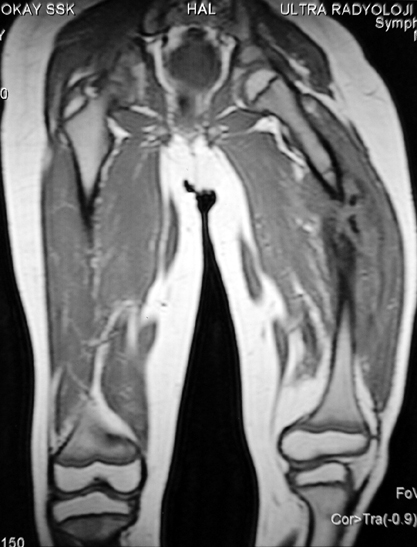

Chronic osteomyelitis leads to necrosis of bone and soft tissues. Dead bone is a nidus which hosts pathogenous microorganisms. Defence mechanisms of the host is usually not in optimum condition to deal with microorganisms. Antibiotics can’t reach the infection site because blood flow is disrupted. For these reasons, dead bone has to be completely removed by radical debridement.

Appropriate radical debridement necessitates excision of all necrotic bone and soft tissues, and frequently causes instability at the involved extremity. The remaining bone and soft tissue defect has to be fixed and reconstructed. The distraction osteogenesis method of Ilizarov is used successfully for achievement of union, correction of the deformity, elimination of limb length inequality and reconstruction of segmental bone defects.

The duration of external fixation (external fixation index) depends on the amount of distraction required, and the extremity is prone to complications during this period. After the distraction phase is completed, the external fixator remains in place during the consolidation phase, which lasts twice as long as the distraction phase; but this period is hardly tolerated. If the external fixator is removed before sufficient consolidation is achieved, fractures, deformity and shortness will be the result. In our department, ‘lenghthening over nail’ method is used in order to decrease the external fixation index and increase patient comfort and activity level. In this method, the intramedullary nail is statically locked after the completion of the distraction phase, and external fixator is removed. The extremity is stabilized by the intramedullary nail during consolidation phase. In this way, complications due to long external fixation index or early removal of the external fixator are avoided.